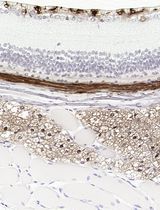

Cover of Cancer Research, featuring study using the protocol.

Jan 2013